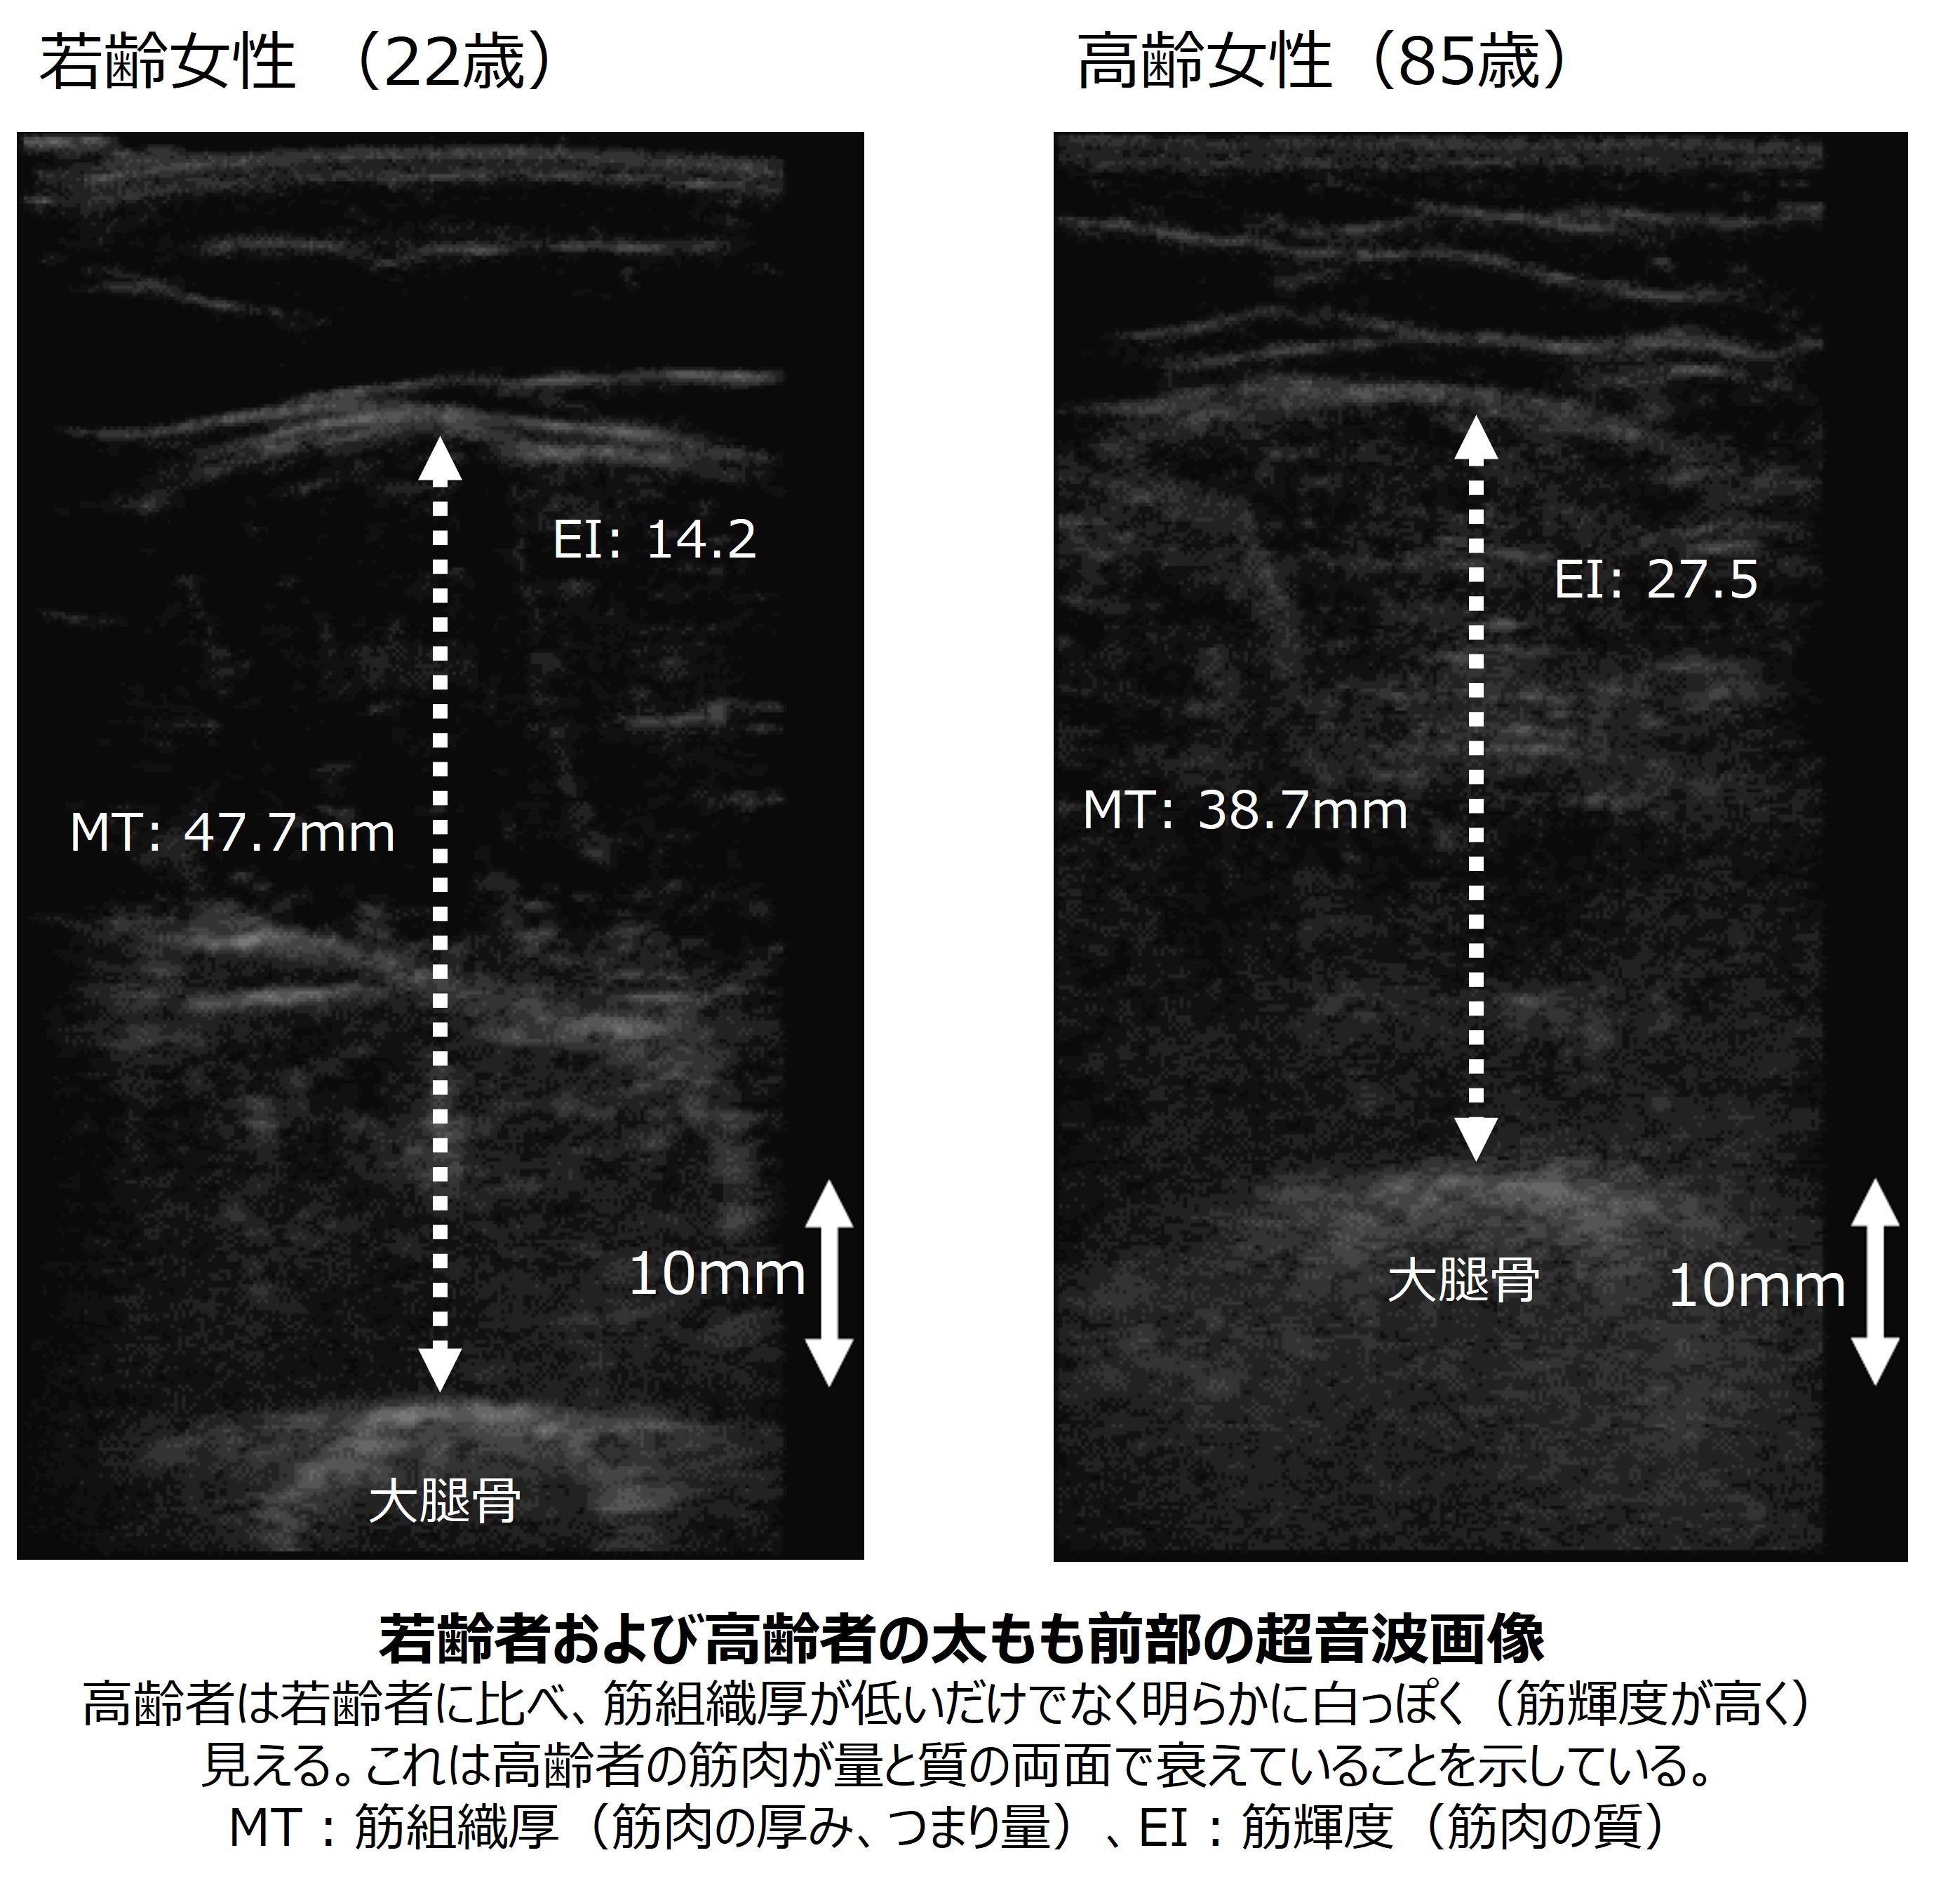

筋肉には、筋線維(筋細胞)のほかに脂肪や水が含まれています。力を発揮する役割を持つ筋線維の密度が高い筋肉が良質です。この筋肉の質を超音波(エコー)画像から評価できます。私は太もも前の筋肉(大腿直筋)を評価しています。画像処理ソフトを使ってターゲットの筋肉を囲むと、その範囲の平均ピクセル輝度(筋輝度、エコー輝度)を取得できます。筋肉の量が運動機能に関連することは容易に想像できますが、筋肉の質も影響を及ぼしています。私の研究では184名の高齢男性のデータを分析し、太もも前の筋肉の質が脚の筋力に影響することが分かりました。

エコー画像(下図参照)で白く映る部分には脂肪などが含まれています。黒に近い部分が多いほど筋肉の質が良いと言えます。